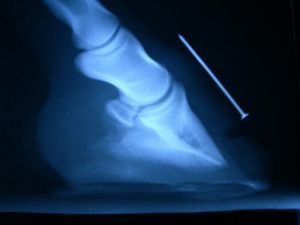

Bohužel krátce nato (v létě 2007) se ocitl na Veterinární klinice v Brně jako prakticky nechodící. Diagnóza zněla akutní schvácení kopyt. Postižené byly všechny končetiny. Na pánevních končetinách bylo poškození mírnější, ale na předních bohužel došlo k tak silné rotaci kopytních kostí, že prorazily chodidlo. Nejhůře na tom byla jeho levá přední. Po vyšetření bylo navrženo jeho utracení.

V jakém stavu byl, když se ti dva poprvé setkali? „Kopytní pouzdro se smekalo na všechny strany, nic nedrželo a vše bolelo a často abscedovalo. Obě kopytní kosti prorazily chodidlo ještě na Univerzitě, takže se lékaři neodvážili ani sundat podkovy, které držely kopytní pouzdro pohromadě. Mirisk s problémy zvládl transport, ale bez velkého nátlaku nebyl schopný udělat ani krok. Špičky kopytních kostí lezly chodidly ven… když jsem to poprvé viděl odvázané, tak jsem raději nemyslel na realitu." Nicméně Miriskovi sundal podkovy a upravil kopyta tak, jak považoval za nejlepší.

Za měřítko úspěšnosti léčebného procesu považuji bezbolestný pohyb. Bezbolestný v rámci možností, ale určitě ne s maskovanou bolestivostí, kterou by zajišťovaly podkovy. Proto je potěšitelné, že zhruba v lednu 2008 se dalo konstatovat, že se hřebec pohybuje ochotně a bez abnormalit ve všech chodech, a to na měkkém i tvrdém hladkém terénu. Postupně rohovina s řezy odrůstala a Miriskova kopyta začínala vypadat jako kopyta ostatních zdravých koní. Bohužel ale Mirisk nezůstal bez následků. Protože se k nám dostal až měsíc po posledním schvácení, došlo k erozi (osteolýze a resorpci špiček) konců kopytních kostí, a to zejména na nejzávažněji poškozené levé přední noze.

rtgPřípad byl prezentován jako kazuistika na výroční konferenci Hipiatrické společnosti a Živnostenského společenství podkovářů v únoru 2008 s tématem Schvácené kopyto. Byl zde mj. přítomen i profesor Robert Eustace z Laminitis Clinic (referenční pracoviště pro schvácené koně pro celou Velkou Británii). On rozdělil případy laminitidy podle přesně definovaných znaků (pokles, rotace kopytní kosti, atd.) do čtyř skupin. První skupinu tvořili nejméně postižení koně, do čtvrté spadaly beznadějné případy. Prezentoval zde statistiku třetí skupiny, kde měl 172 koní. Z nich pouze čtyři se povedlo zachránit pro další hodnotný život a pouze jeden se vrátil k jakémusi stupni sportu. Podle jeho rozdělení patřil do této třetí skupiny i Mirisk. Právě v jeho případě se profesor Eustace a přítomný dr. Hans Castelijns shodli, že nic nebrání jeho dalšímu jezdeckému využití. Sportovní, především skokové zatížení nedoporučili, určitou výjimkou jsou dostihy, kterých by snad s dobrým podkováním byl schopen.